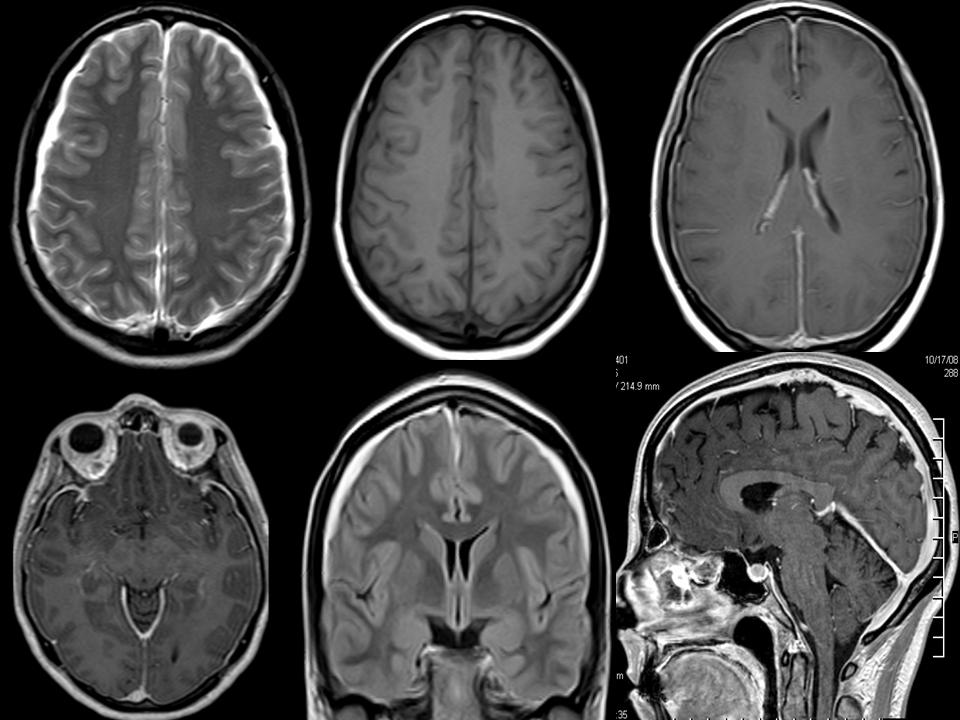

Nöro-Behçet MRParenkimal Nöro-Behçet hastalığı nedir?

Bu terim Behçet hastalığının özellikle beyin ya da omurilik dokusunda hasar oluşturduğu zaman kullanılmaktadır. Behçet hastalığı en sıklıkla parenkim tutulumu ile nörolojik bulgu oluşturmaktadır. Bu durumda beyinin özellikle beyin sapı denen bölgesinin tuttulduğu için hastalarda çift görme, felçler, dengesizlik ve peltek konuşma gibi belirtiler izlenmektedir. Hastalarda parenkimal tutulum düzeldikten sonra tekrar edebilme ihtimali olduğu için en az 5 yıllık koruma tedavisinin verilmesi önerilir. Bu süre ağır giden hastalarda daha da uzatılabilmektedir.

Nöro-Behçet MRParenkimal Nöro-Behçet hastalığı nedir?

Bu terim Behçet hastalığının özellikle beyin ya da omurilik dokusunda hasar oluşturduğu zaman kullanılmaktadır. Behçet hastalığı en sıklıkla parenkim tutulumu ile nörolojik bulgu oluşturmaktadır. Bu durumda beyinin özellikle beyin sapı denen bölgesinin tuttulduğu için hastalarda çift görme, felçler, dengesizlik ve peltek konuşma gibi belirtiler izlenmektedir. Hastalarda parenkimal tutulum düzeldikten sonra tekrar edebilme ihtimali olduğu için en az 5 yıllık koruma tedavisinin verilmesi önerilir. Bu süre ağır giden hastalarda daha da uzatılabilmektedir.